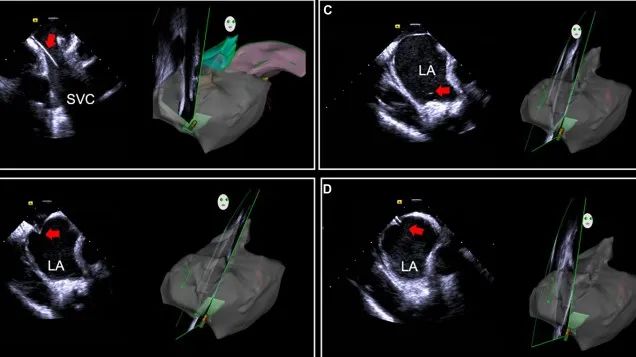

一種與心導(dǎo)管檢查相結(jié)合的超聲心動圖診斷新興技術(shù),通過將超聲探頭置于心腔內(nèi)部,發(fā)射并接收超聲信號,來精確獲取心臟解剖結(jié)構(gòu)、心臟血流動力學(xué)等信息的實(shí)時成像。與其他影像技術(shù)相比,ICE技術(shù)具有操作簡單、無輻射、安全性高、手術(shù)效率高、實(shí)用等優(yōu)勢,ICE在很大程度上有望取代經(jīng)食道超聲心動圖(TEE),成為電生理和結(jié)構(gòu)性心臟病領(lǐng)域的理想成像方式。

目前ICE技術(shù)已被應(yīng)用于左心耳封堵、房顫射頻消融、二尖瓣成形、房間隔缺損封堵等多種心臟介入手術(shù),應(yīng)用場景主要圍繞心臟電生理、結(jié)構(gòu)性心臟病等領(lǐng)域,目前以電生理應(yīng)用為主。數(shù)據(jù)顯示,我國結(jié)構(gòu)性心臟病介入器械市場規(guī)模已從2017年的4億元增長至2021年的20億元,年復(fù)合增長率達(dá)48.3%;預(yù)計到2025年,該市場規(guī)模將達(dá)到104億元,可以預(yù)見ICE市場規(guī)模也將同步高速增長,未來市場發(fā)展空間廣闊。

心腔內(nèi)超聲(ICE)技術(shù)壁壘極高,國內(nèi)主要廠商核心部件仍舊為進(jìn)口,集成了超聲和圖像處理最前端技術(shù),包括超聲探頭、線纜、軟件成像算法等,是當(dāng)前內(nèi)窺超聲方向最具挑戰(zhàn)的領(lǐng)域。ICE的應(yīng)用經(jīng)歷了2D平面成像、3D三維立體成像、以及4D的實(shí)時三維立體成像階段。